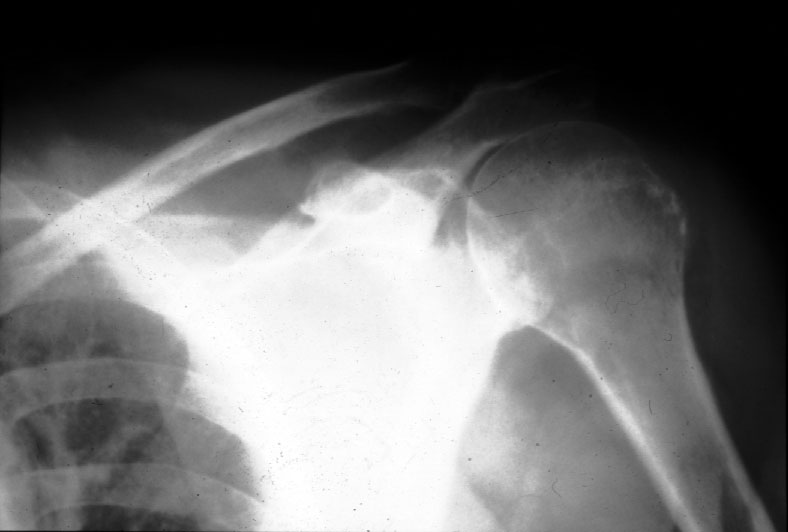

Normal Shoulder (frontal) -- Identify: clavicle, acromion process, glenoid,

humeral head